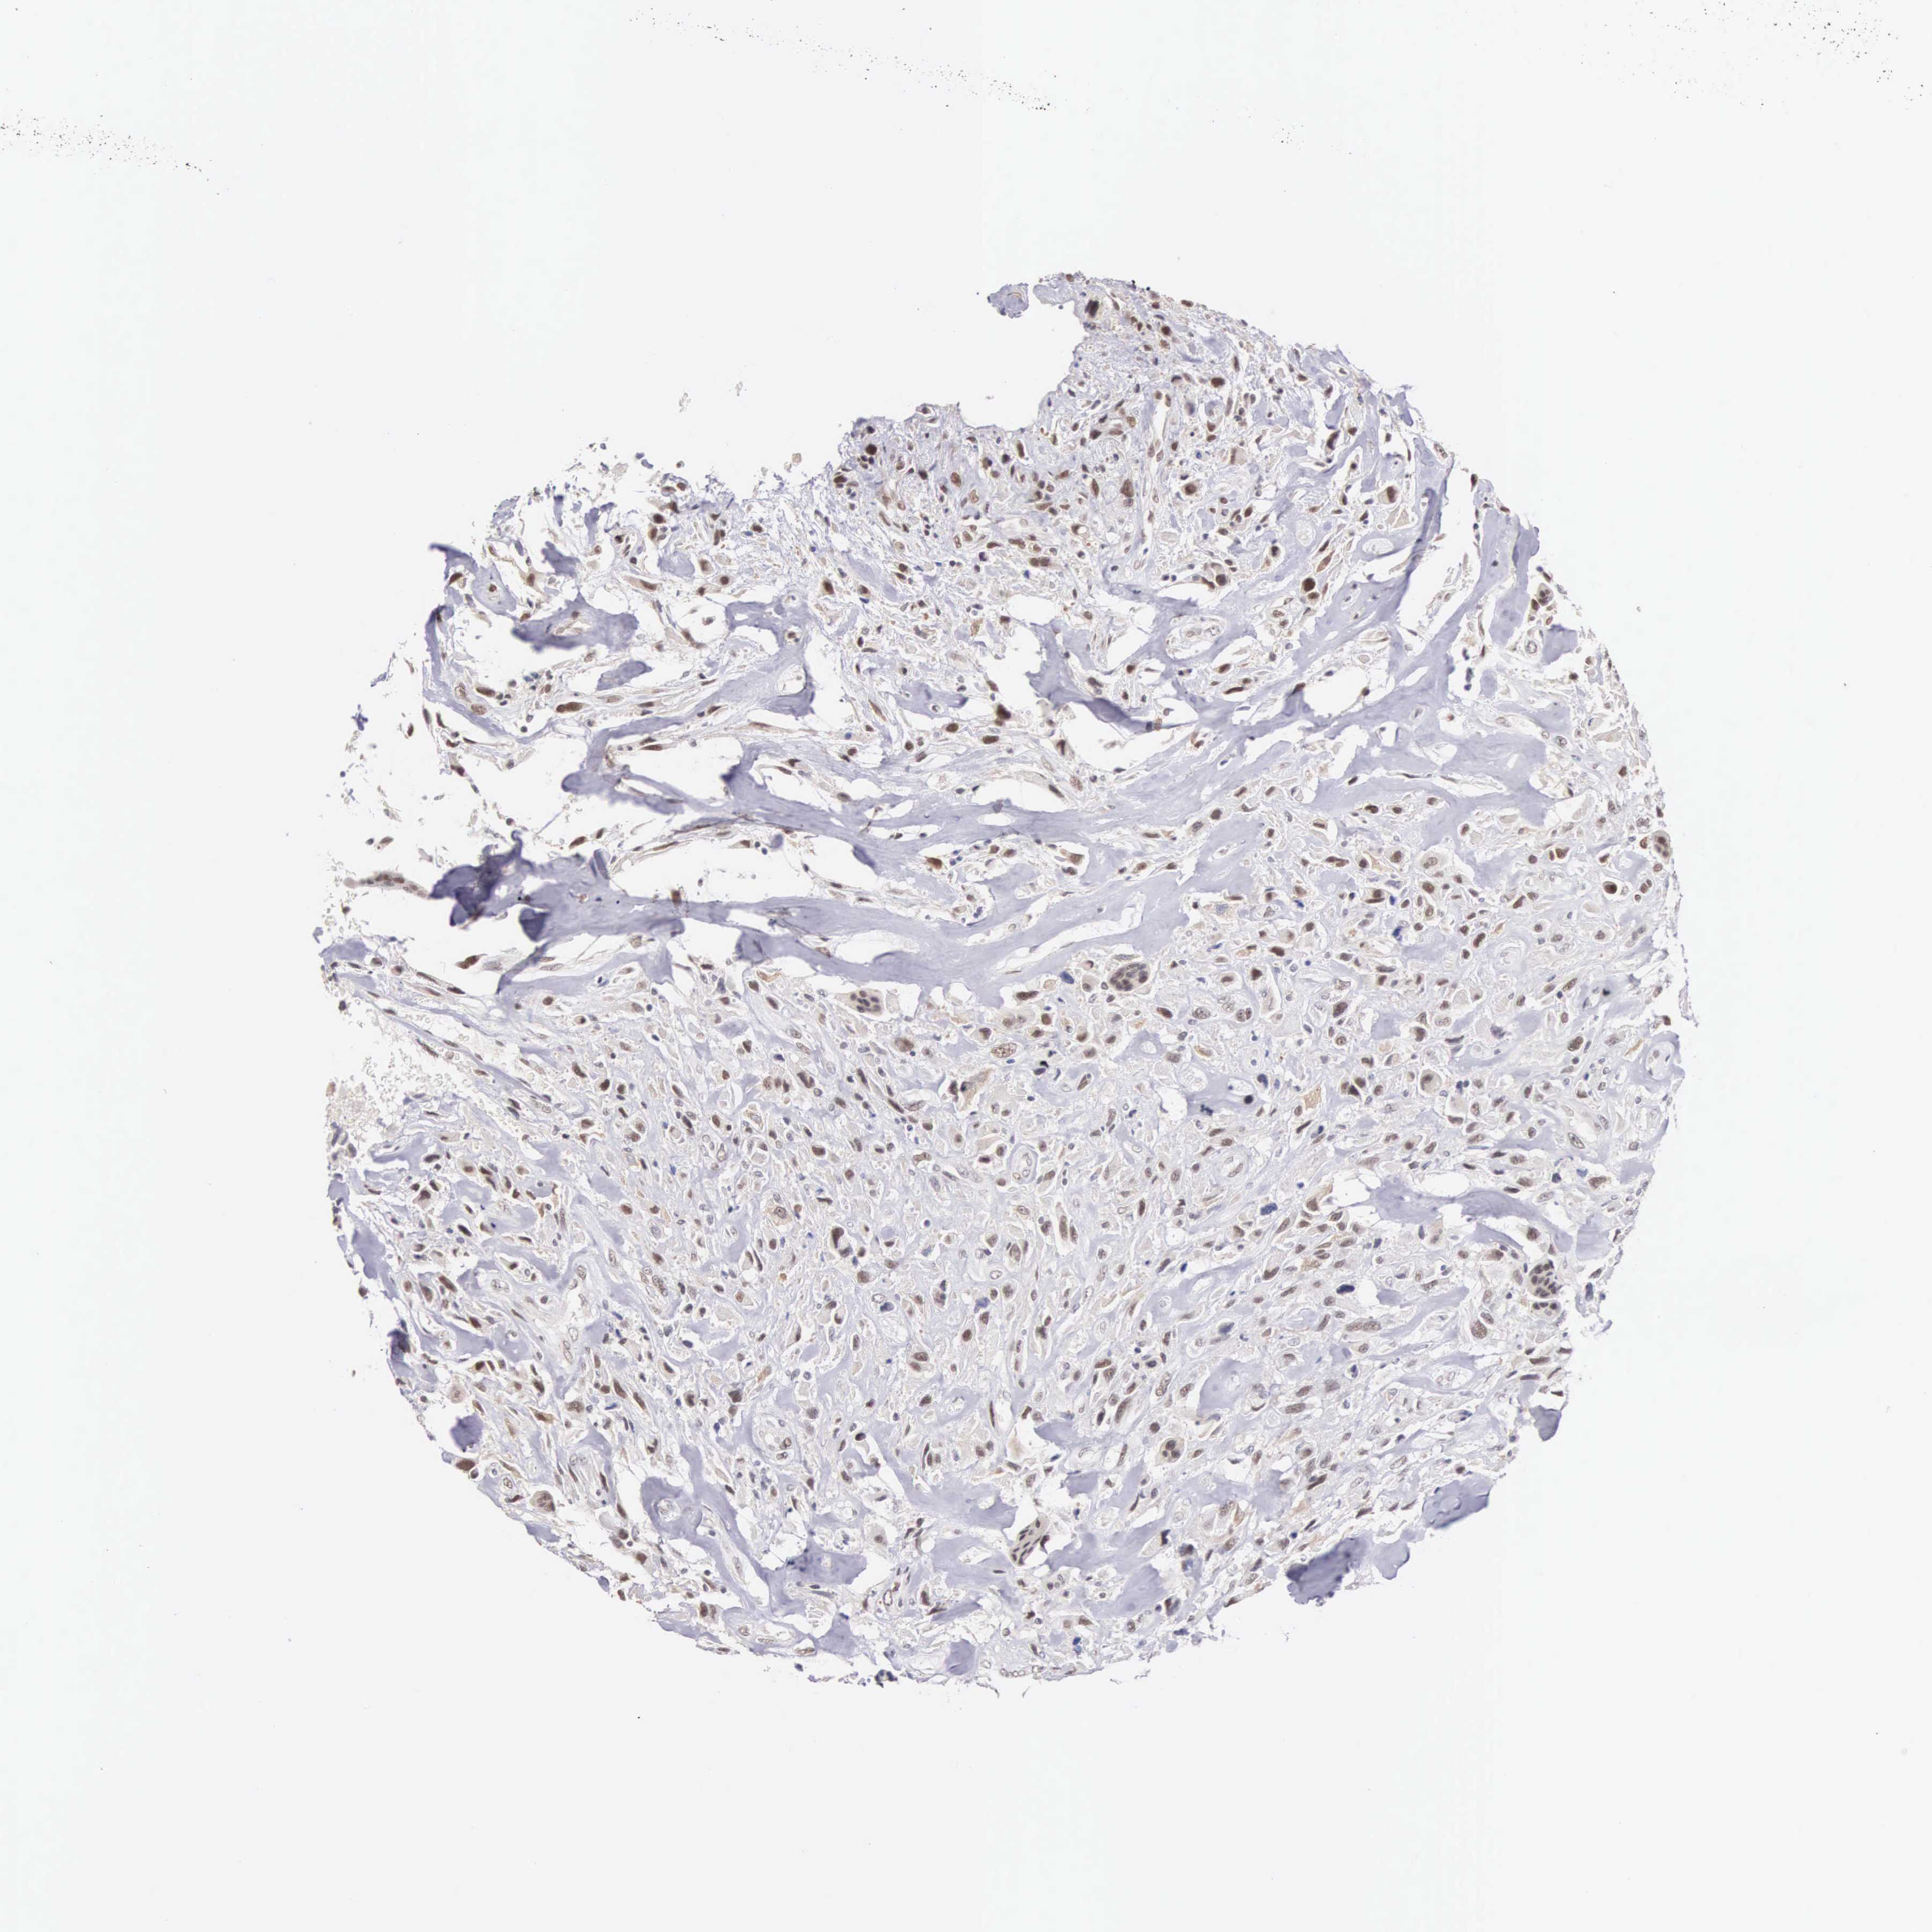

BRCA TCGA BRCA VALIDATION PROTEIN EXPRESSION

Breast cancer

Human cancer

Breast invasive carcinoma